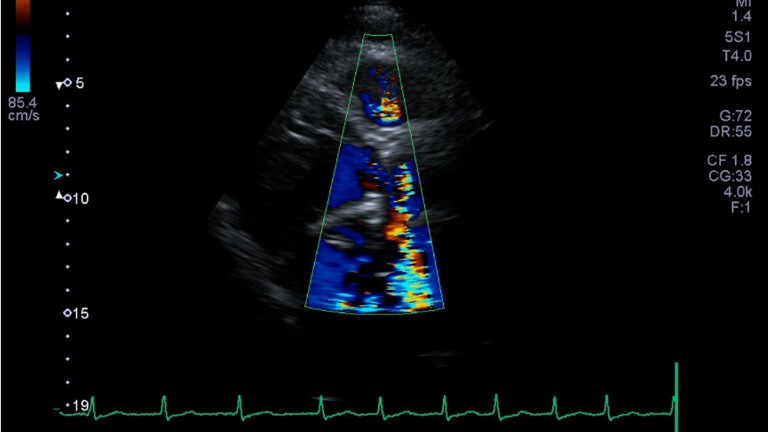

CT stress perfusion is performed to demonstrate how well blood flows throughout the heart muscle. The presence of a narrowed coronary artery can affect blood flow, resulting in downstream changes in the heart muscle that can be assessed qualitatively and quantitatively using CT stress perfusion. During the examination, a specific drug is administered intravenously (into a vein) to redistribute the flow of blood in the heart. This drug works by dilating the small blood vessels in the heart, comparable to exercising and can result in an increase in heart rate and a feeling of shortness of breath. European Scanning Centre is the only UK centre performing this investigation with images reported by Dr Ceri Davies, Cardiac imaging lead at Barts Health.

Diagnostic imaging plays a central role in the care of patients with structural heart disease, with high quality imaging required for the diagnosis, pre procedural planning, device sizing and post-procedural assessment. Cardiac CT is an essential investigation for structural and valvular heart disease assessment.